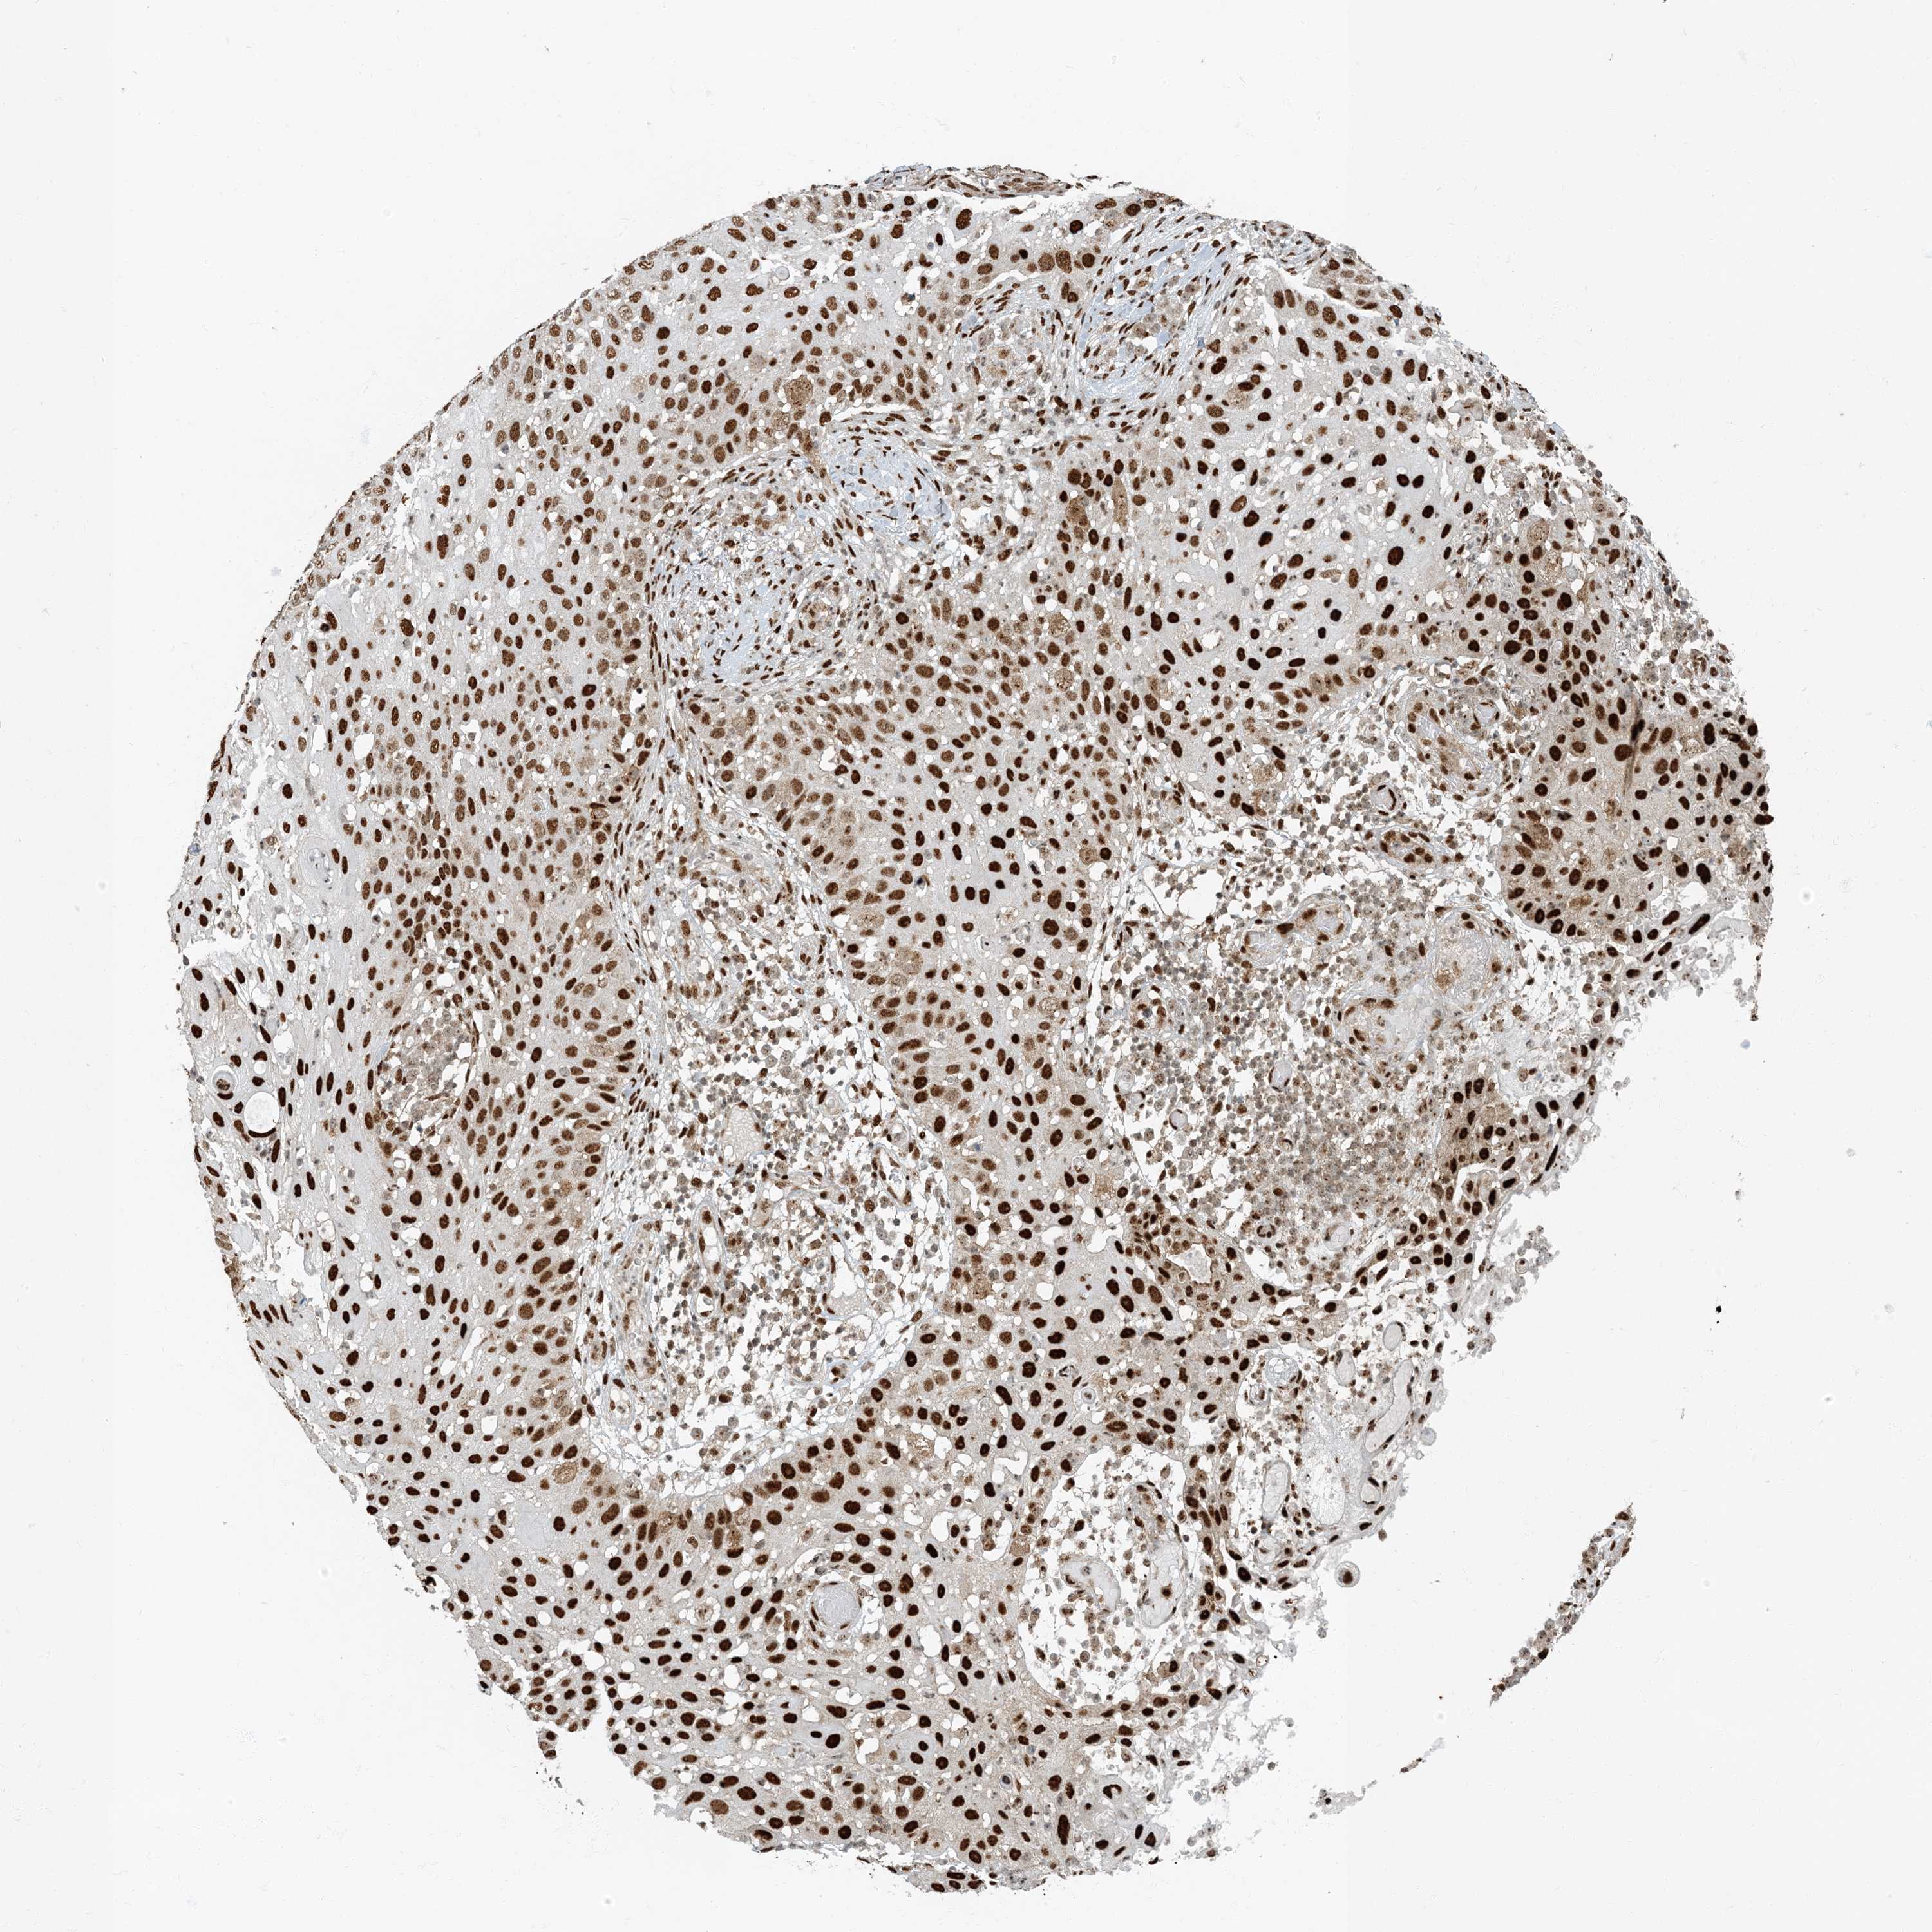

SKIN CANCER - Protein expressioni

A mouse-over function shows sample information and annotation data. Click on an image to view it in a full screen mode. Samples can be filtered based on level of antibody staining by selecting one or several of the following categories: high, medium, low and not detected. The assay and annotation is described here.

Each image is clickable and will lead to virtual microscopy that enables deeper exploration of all samples and also displays staining intensity scores, fraction scores and subcellular localization as well as patient and tissue information for each sample.

Antibody CAB009017

Staining

Medium

Intensity

Moderate

Quantity

75%-25%

Location

Nuclear

Squamous cell carcinoma, NOS